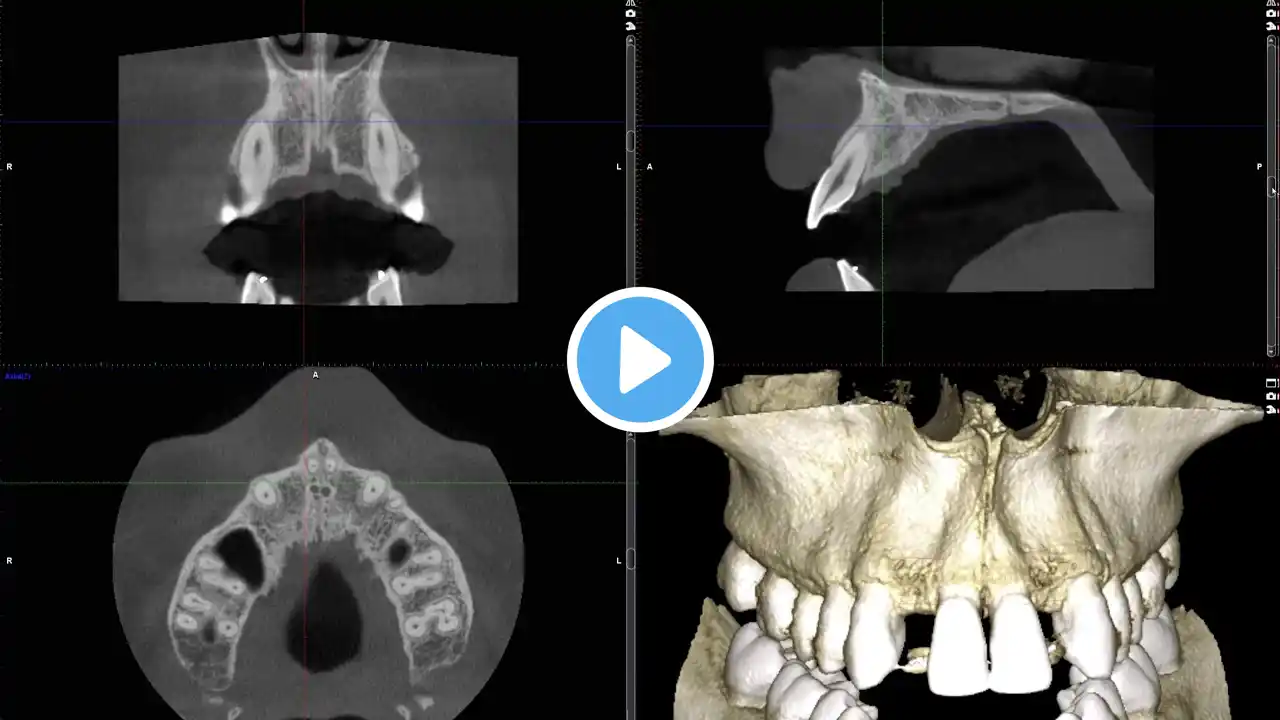

Missing Lateral Implant

Implant planning for congenitally missing lateral incisors